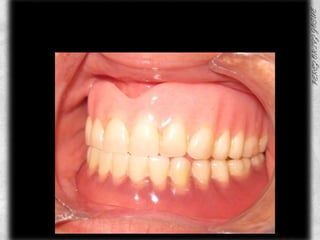

PROTESIS TERMINADA

AJUSTE OCLUSAL

COMPARATIVOS